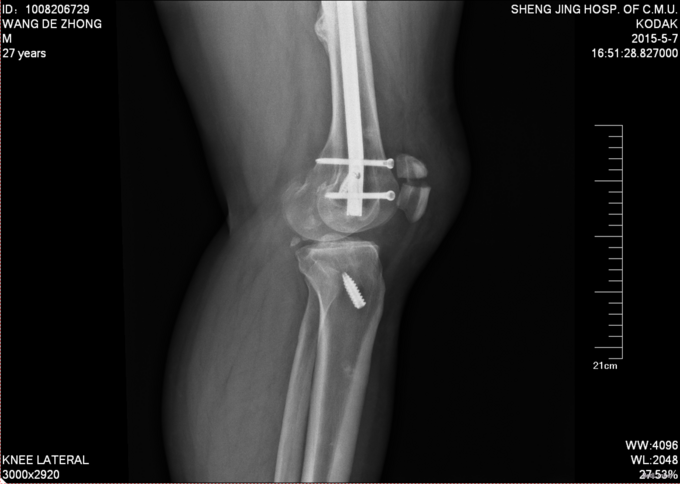

主诉:外伤后膝关节疼痛、活动受限8小时 患者8小时前打架被人钝器砸到膝关节后出现左下肢疼痛、活动受限、不能行走,受伤后意识清醒,略有头晕头迷。受伤后于我院急诊就诊,完善相关检查后以“髌骨骨折”为诊断收入院。患者目前一般状态可,无发热寒战,无恶心呕吐,受伤以来饮水未进食,未排气大便,小便如常。

专科查体:患者平车推入病房,左膝关节肿胀明显,活动障碍,左足足背动脉可触及,脚趾活动好,皮肤感觉无麻木。

诊断:左髌骨骨折 患者入院后见患肢肿胀明显,给予患肢抬高位,冷敷,甘露醇消肿等对症治疗,带患肢出现褶皱试验阳性后,全麻下行左髌骨骨折切开复位张力带内固定术,术后患者肿胀明显,给予抗炎,消肿,冷敷,患肢抬高等对症治疗。患者每天换药观察切口愈合情况,无红肿及渗出,待伤口14天后予以拆线治疗,予以出院,给予康复处方。